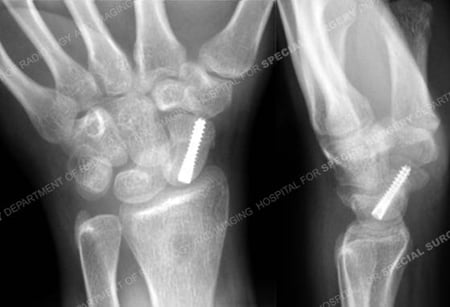

Anteroposterior and lateral radiographs at 6 months illustrating a healed scaphoid fracture.